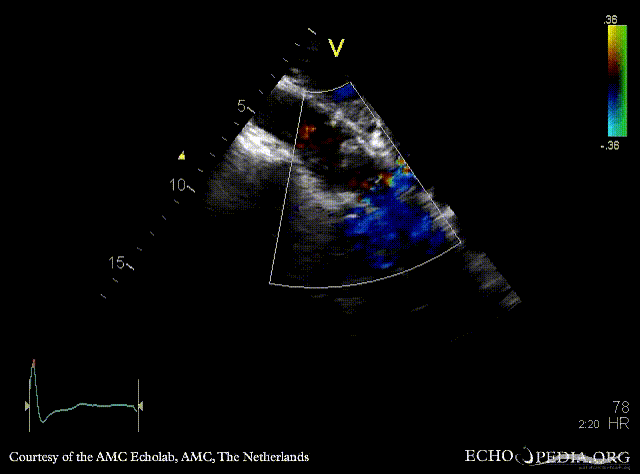

| PSAX: stenosis of aortic valve | PLAX with Color Doppler: high velocity transaortic flow, mild aortic regurgitation |